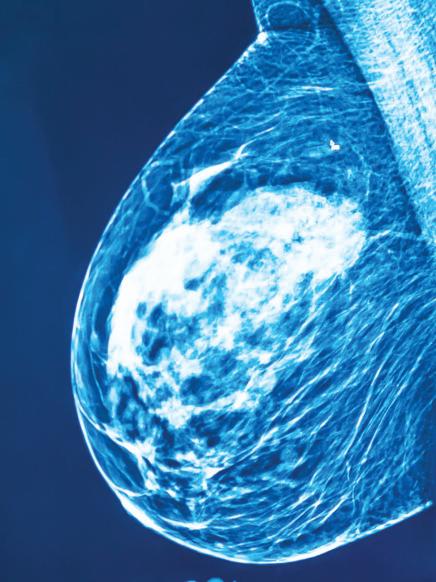

Revista Puertorriqueña de Medicina y Salud Pública8 MANEJO DECÁNCER DE PRÓSTATA: Prostatectomía Radical Laparoscópica 2D frente a la Prostatectomía Radical Laparoscópica 3DHD

Propósito: Nuestro estudio compara los resultados perioperatorios entre la prostatectomía radical laparos cópica (LRP) bidimensional (2D) y la LRP tridimensional / de alta definición (3DHD) de 4ª generación. Métodos: Se evaluaron los datos adquiridos retrospectiva mente de pacientes que se sometieron a LRP 2D (n = 75) y LRP 3DHD (n = 75) desde marzo de 2013 hasta octubre de 2015. Los procedimientos fueron realizados por un solo cirujano. Se utilizó el abordaje extraperi toneal con 5 trócares. Los resultados perioperatorios, la potencia y la continencia se compararon entre los grupos. Resultados: Las características de los pa cientes fueron similares entre los dos grupos en cuanto a edad (p=0,44), niveles de antígeno prostático es pecífico (PSA) (p=0,34) y puntuaciones de Gleason (p=0,14). El índice de masa corporal (IMC) fue signi ficativamente mayor en el grupo 3DHD (p=0,0036). Después de la operación, no se observaron diferen cias significativas en la pérdida de Hgb (p = 0,50), los márgenes quirúrgicos positivos (p = 1,00) y las puntuaciones de Gleason postoperatorias (p = 0,30). Se observaron diferencias significativas en cuanto a la duración de la estancia hospitalaria (p<0,001) y el drenaje de Jackson-Pratt (JP) (p<0,001). En cuanto a la potencia, el 73,7% y el 51,6% de los pacientes en los grupos 3DHD y 2D recuperaron la potencia a los 6 meses, respectivamente (p=0,0025). Casi el 43% de los pacientes en el grupo 3DHD recuperaron la conti nencia a 1 mes, mientras que para los grupos 2D fue solo el 17,3% (p = 0,0008). Conclusión: 3DHD y 2D LRP han resultado en buenos resultados en los pe ríodos perioperatorios. Nuestros resultados muestran una disminución del drenaje de JP, una menor duración de la estancia hospitalaria, un retorno más temprano del control urinario y un retorno más temprano de la función sexual en el grupo de LRP 3DHD. En centros de menor volumen donde el equipo de robótica no es factible debido a las barreras económicas, 3DHD se puede realizar de manera segura como una alternati va mínimamente invasiva.

ABSTRACT

Purpose: Our study compares periope rative outcomes between two-dimensional (2D) laparoscopic radical prostatectomy (LRP) and 4th generation three-dimen sional/high-definition (3DHD) LRP. Methods: Retrospectively acquired data from patients who underwent 2D LRP (n = 75) and 3DHD LRP (n = 75) from March 2013 to October 2015 were evaluated. Procedures were performed by a single surgeon. The extraperitoneal approach with 5 trocars was used. Perioperative outcomes, potency, and continence were compared between groups. Results: Pa

tient characteristics were similar between the two groups in terms of age (p=0.44), prostate-specific antigen (PSA) levels (p=0.34), and Gleason scores (p=0.14). ). Body mass index (BMI) was significantly higher in the 3DHD group (p=0.0036). Postoperatively, no significant differences were observed in Hgb loss (p = 0.50), positive surgical margins (p = 1.00), and postoperative Gleason scores (p = 0.30).

Significant differences were observed for length of hospital stay (p<0.001) and Jackson-Pratt (JP) drainage (p<0.001). Regarding potency, 73.7% and 51.6% of patients in the 3DHD and 2D groups re

gained potency at 6 months, respectively (p=0.0025). Almost 43% of the patients in the 3DHD group regained continence at 1 month, while for the 2D groups it was only 17.3% (p = 0.0008). Conclusion: 3DHD and 2D LRP have resulted in good results in the perioperative periods. Our results show decreased JP drainage, shorter len gth of hospital stay, earlier return of uri nary control, and earlier return of sexual function in the LRP 3DHD group. In lower volume centers where robotics equipment is not feasible due to economic barriers, 3DHD can be performed safely as a mini mally invasive alternative.

El cáncer de próstata es el cáncer más común diagnosticado en los hombres y la segunda causa principal de muertes re lacionadas con el cáncer en los Estados Unidos. Se estima que 268,490 hombres serán diagnosticados y 34,500 hombres morirán de cáncer de próstata en 2022 [1]. En 2020, casi 1,4 millones de hom bres fueron diagnosticados con cáncer de próstata, lo que representa el 15% de los cánceres diagnosticados en hombres de todo el mundo. Los países menos de sarrollados tienen una menor incidencia pero mayores tasas de mortalidad por cáncer de próstata que los países más desarrollados (Australia/Nueva Zelanda, América del Norte, Europa). Tangen et al. (2012) afirmaron que el uso de herra mientas de detección como las pruebas de antígeno prostático específico (PSA) y los tratamientos mejorados en los países más desarrollados permite una detección más temprana del cáncer de próstata y una disminución de las tasas de morta lidad [2].

Puerto Rico posee una población es timada de 3.200.000 habitantes. Los puertorriqueños son particularmente vul nerables a las disparidades del cáncer debido a las cualidades socioeconómi cas. En 2020, aproximadamente el 44% de la población en Puerto Rico vivía en la pobreza, en comparación con el 17% de los hispanos estadounidenses y el 9% de los blancos no hispanos (NHW) que viven en los Estados Unidos continenta les. Chinea et al. (2017) [3] informaron que los subgrupos hispanos/latinos (H/L) tienen diferentes tasas de mortalidad es pecífica por cáncer de próstata (PCSM) en comparación con los hombres negros no hispanos (NHB) de NHW, utilizan do datos de 2000-2013 que incluyeron 486,865 hombres. Las tasas de inciden cia y mortalidad por cáncer de próstata (PCa) en hombres H/L fueron similares a las de NHW; sin embargo, los hombres puertorriqueños hispanos/latinos (PR H/L) tenían un PCSM significativamente más alto que el NHW y tenían la mayor mortalidad entre los subgrupos hispanos. En 2018, la tasa general de incidencia de PCa en Puerto Rico fue de 145.2 ca sos por 100,000 habitantes y una tasa de mortalidad ajustada por edad de 18.2 muertes por cada 100,000 habitan tes (Figura 1).

Tenemos como objetivo avanzar signifi cativamente en la investigación de la bio logía del cáncer de próstata letal (PCa) y además reducir la carga de las dispa ridades de salud de PCa en los hombres puertorriqueños hispanos / latinos (PR H / L). El PCa es el cáncer más prevalente, tanto en términos de incidencia como de mortalidad en Puerto Rico. En este escri to exponemos una técnica costo efectiva para tratar a pacientes con cáncer de próstata. Esto tomando en consideración la importancia de proveer la mejor tecno logía de tratamiento posible a población con desventajas económicas.